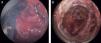

Como utillaje de CET se utilizó el TEO (transanal endoscopic operation, K Storz, Alemania). Se procedió a la resección circunferencial del prolapso, mediante el bisturí ultrasónico (Ultracision, Ethicon, Endo-Surgery, Cincinnati, Ohio, Estados Unidos) abarcando toda la pared rectal, hasta la grasa perirrectal. La exéresis se realizó en 2 fases. En la primera, se marcó una circunferencia a unos 7cm del margen anal (fig. 1B). Se inició la exéresis circunferencial, desde la línea pectínea hasta la zona señalada. Una vez finalizada esta fase se reintrodujo el rectoscopio hasta el límite de resección y se marcó otra circunferencia hasta unos 5cm más allá de los puntos de referencia que se habían marcado al inicio, con la exteriorización de todo el prolapso (fig. 2A). Se volvió a realizar una nueva exéresis circunferencial de toda la pared rectal. No existió perforación en cavidad abdominal ni sangrado significativo.

Se practicó lavado de toda la zona cruenta con solución de povidona yodada diluida al 1%, dejando 2 puntos de referencia en el extremo proximal (zona de recto-sigma) (fig. 2B). Se confirmó la fácil aproximación del borde rectosigmoideo a la línea pectínea (fig. 3A). Se inició la reconstrucción con anastomosis circular realizada con sutura continua monofilamento reabsorbible de larga duración, (MonoPlus®, B. Braun Sutures. Melsungen AG, Germany) de 3/0. Para la consecución de la misma se realizaron 3 semicircunferencias, posterolateral derecho, posterolateral izquierdo y anterior, según técnica habitual de cirugía endoscópica transanal7 (fig. 3B). En el inicio de cada una de estas semicircunferencias los puntos se fijaron a la pared de la pelvis, para que establecieran una fibrosis sobre la misma.